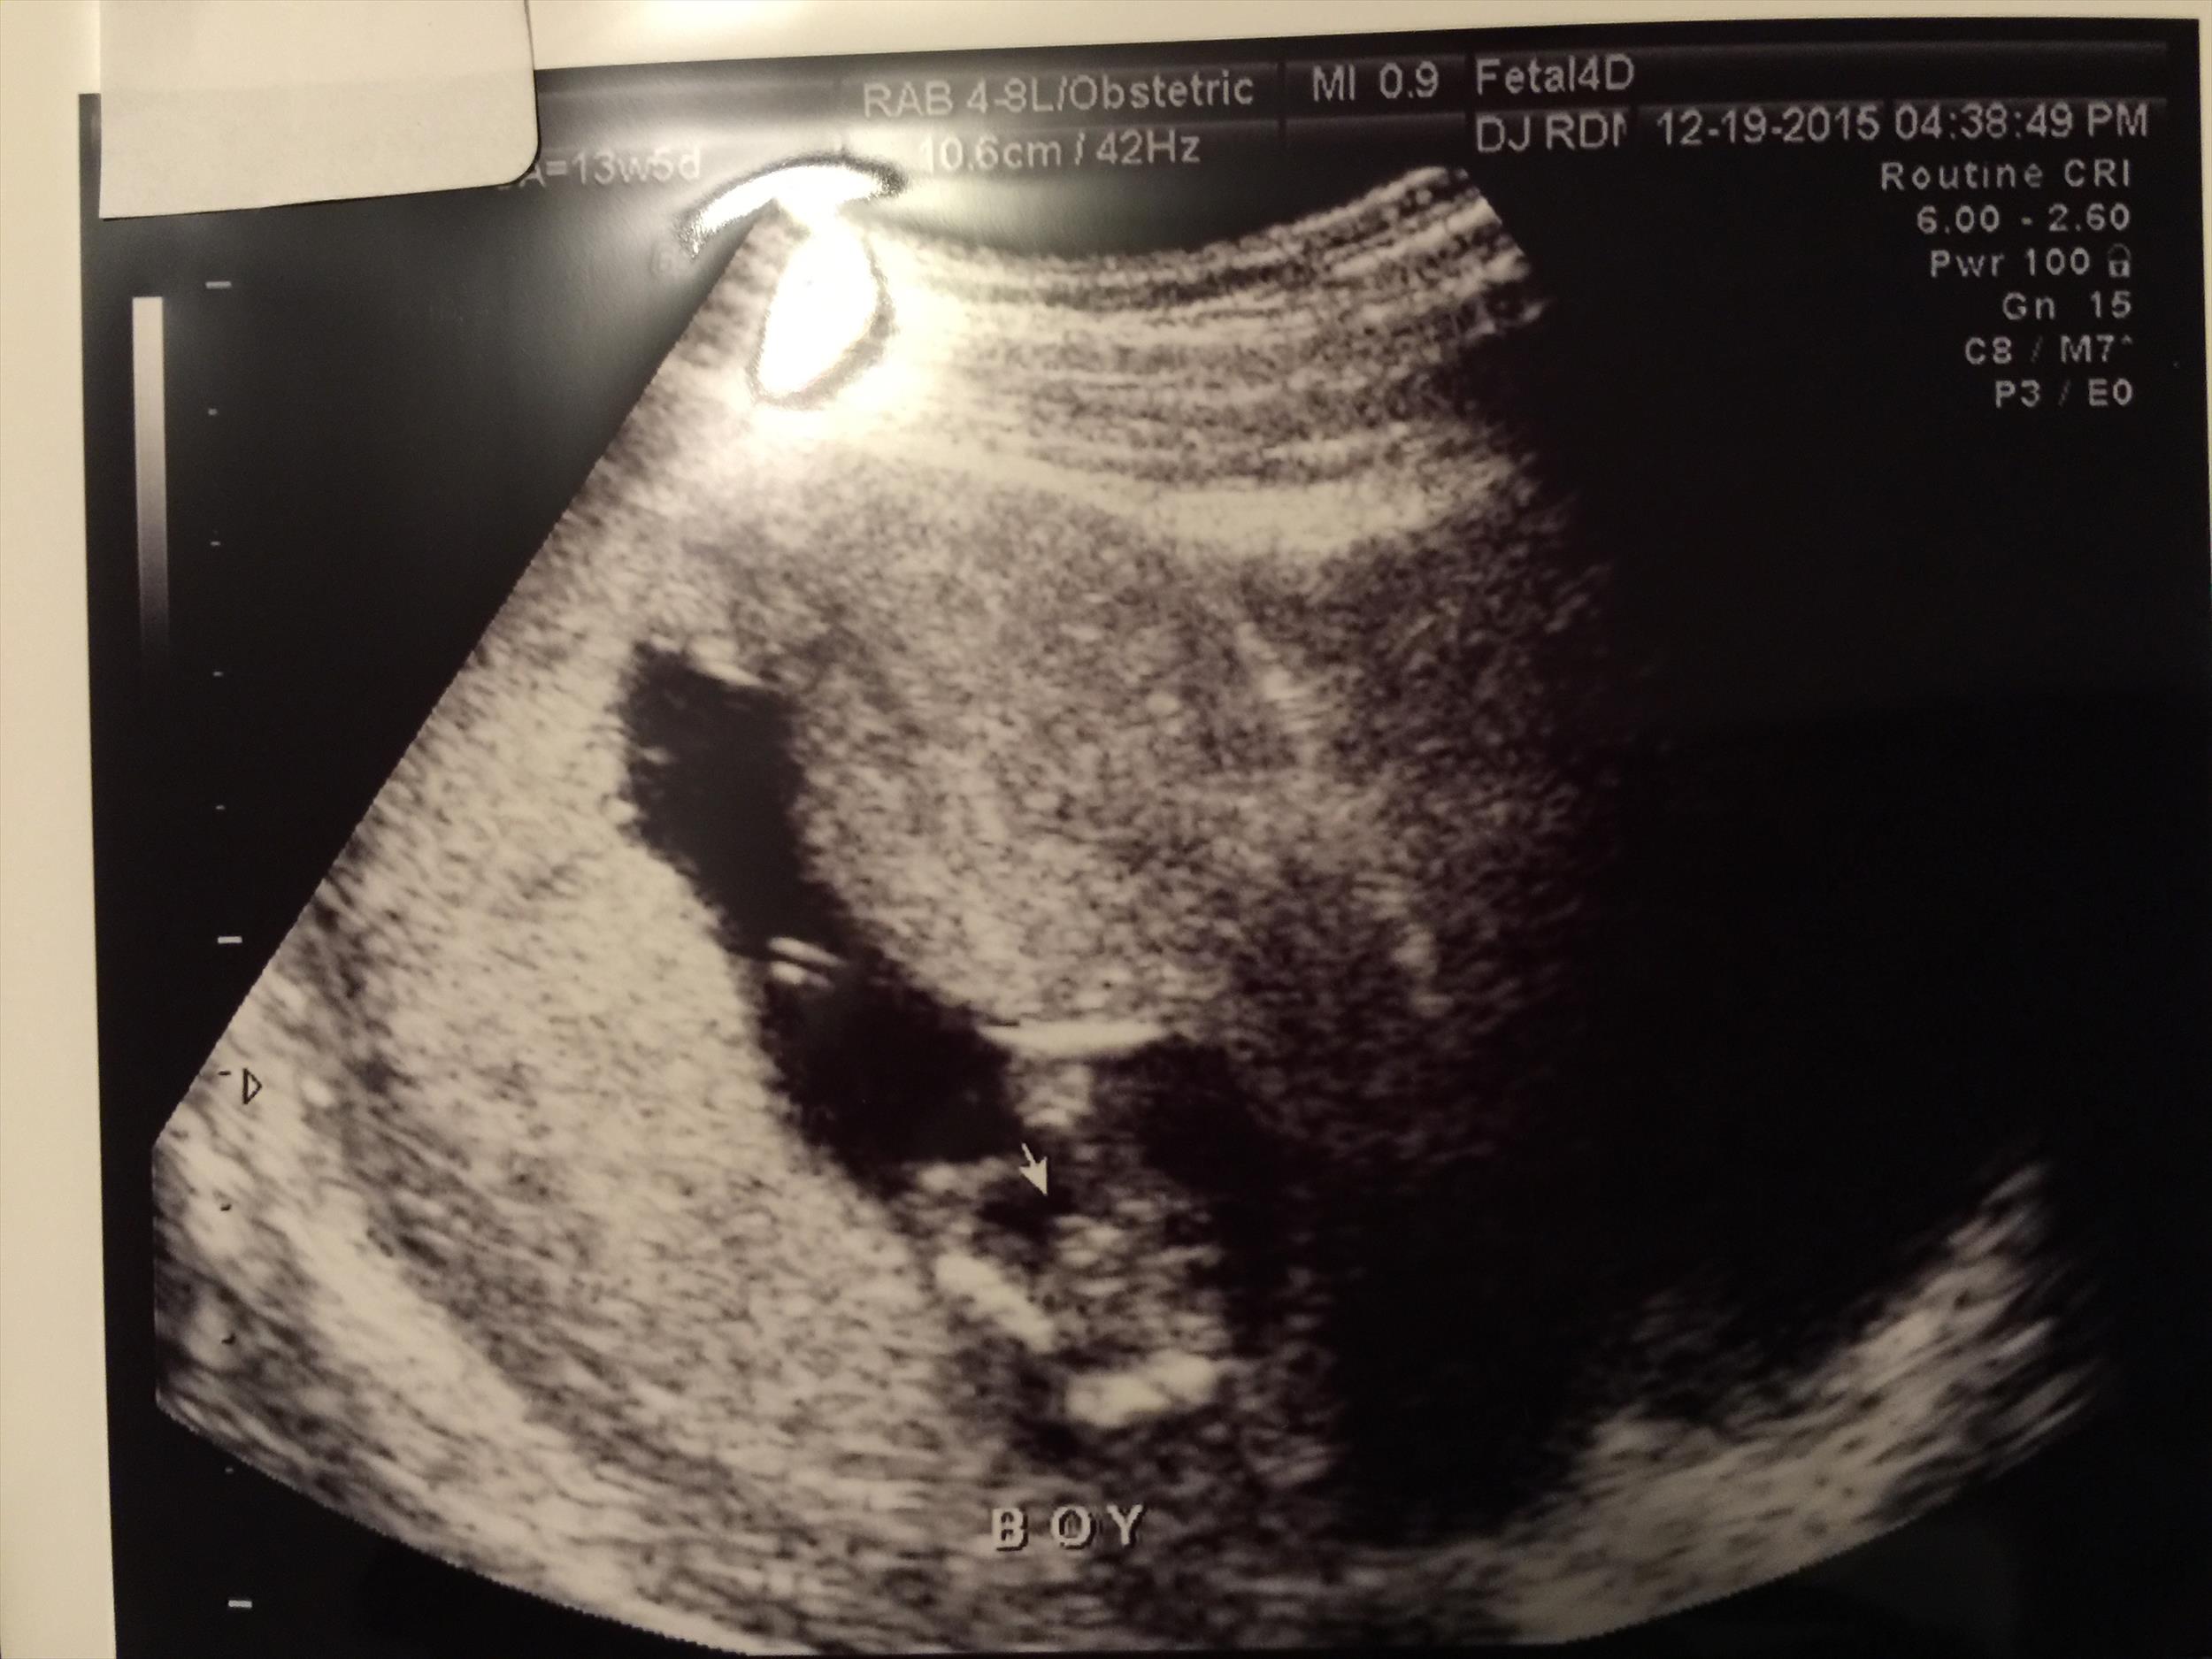

Just got a gender ultrasound at 13wk5d. Sonographer says "boy" but I wanted to make sure she didn't make a mistake. Please let me know if it's pretty obvious in these pictures. Thanks so much :)